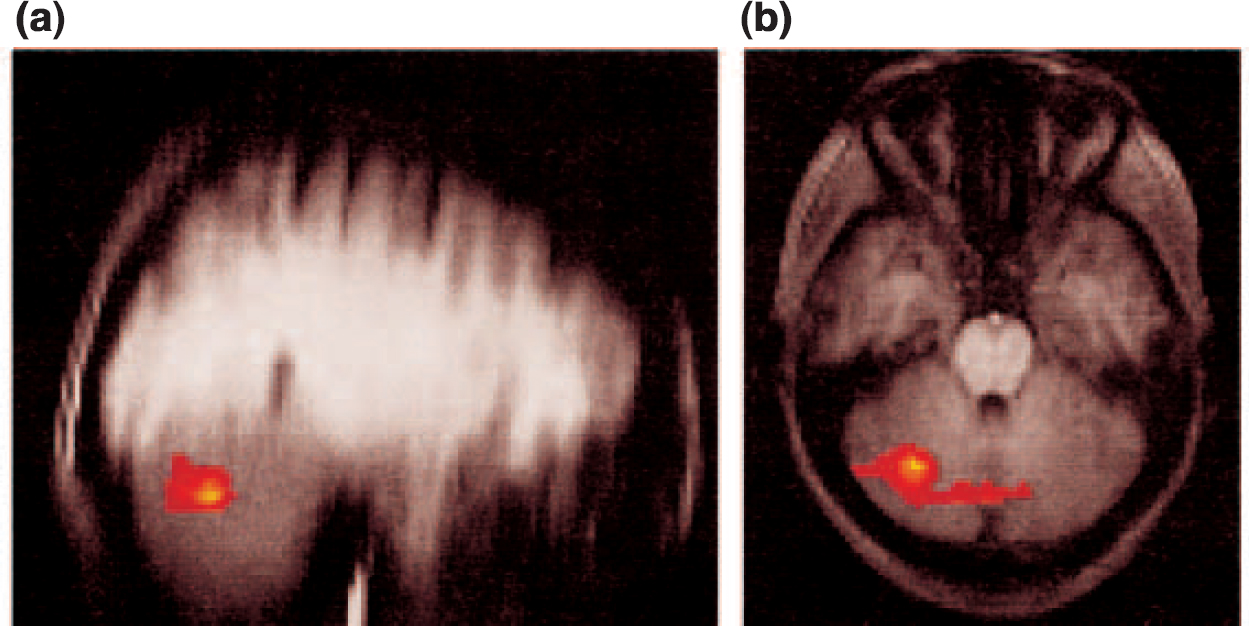

To investigate differences between the two groups in activation to noxious heat and non-noxious warm stimulation during the conditioning period, an analysis was performed comparing activation during anticipation of painful stimulation with activation during anticipation of non-noxious warm stimulation for the two groups. Direct contrast identified significant differences between controls and subjects recovered from depression in the lateral cerebellum and the cerebellar vermis (Fig. 3). Direct measurement of the absolute signal intensities revealed a higher cerebellar response with anticipation of pain relative to warmth (mean signal intensity increase in group images, 0.4%) in the controls relative to those recovered from depression (mean signal intensity increase, 0%).

Fig. 3 Fixed-effects analysis of the differences in group responses between healthy controls and subjects recovered from depression to the noxious (painful) and non-noxious (warm) stimuli during the conditioning phase. The activation differences are shown on (a) sagittal and (b) axial slices. These differences demonstrate a reduced conditioning phase response in the subjects that had recovered from depression.